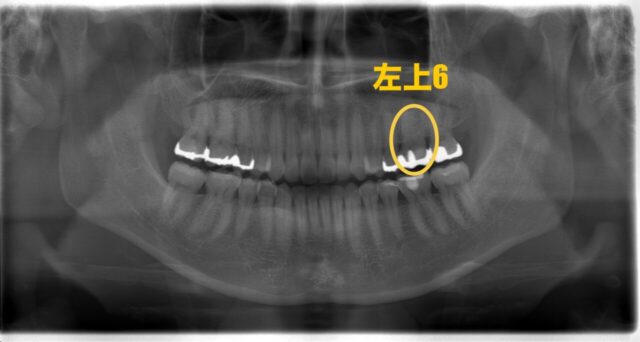

まずはレントゲン写真と口腔内写真をご覧下さい

今回の部位は左上6番です

大きく部分的な詰め物が入っていますね。前回のブログでも紹介した、禁忌のMODインレーが入っています、、

レントゲン写真、CTでも見てみましょう

黄色く囲っているところはカリエスで、青く囲っているところは根尖病変ができてしまっているところです。